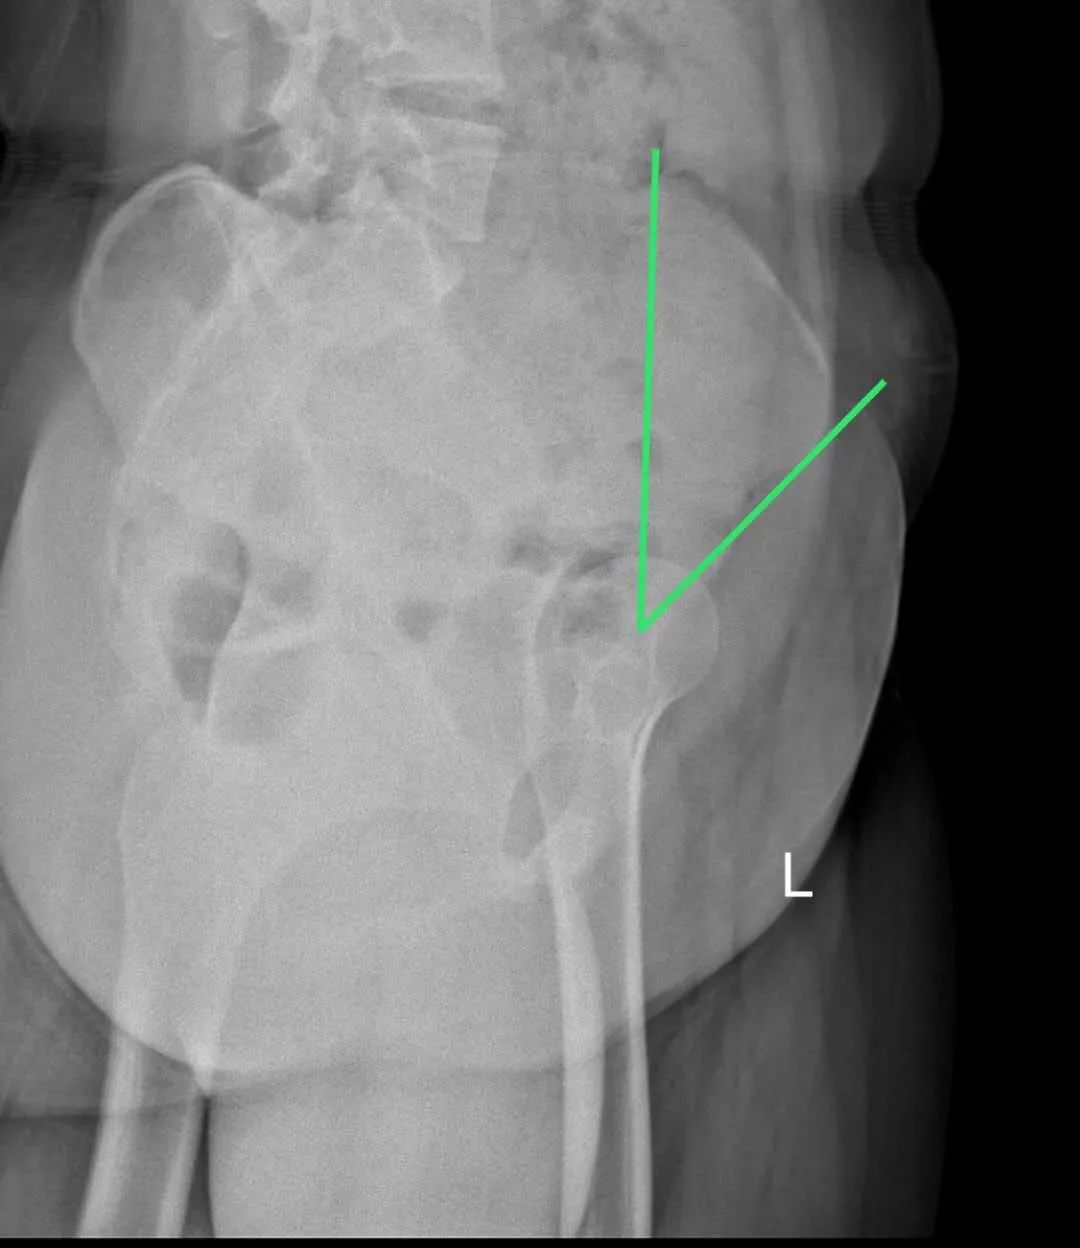

今年15歲的孫某,出現(xiàn)雙側(cè)髖部疼痛,呈持續(xù)性隱痛,只采取口服藥物的保守治療,但是疼痛未見減輕反而愈演愈烈,于是到誠德骨科醫(yī)院集團(tuán)(市中院區(qū))尋求專家的幫助,經(jīng)過多方檢查和論證后,劉德俊院長診斷為:

先天性多發(fā)性骨骺發(fā)育不良,并決定為其實施“髖臼周圍截骨術(shù)”。

據(jù)了解,髖關(guān)節(jié)發(fā)育不良是引起繼發(fā)性髖關(guān)節(jié)炎的重要致病因素之一,髖臼周圍截骨術(shù)能夠有效改善髖臼覆蓋、增加負(fù)重關(guān)節(jié)面,內(nèi)移髖關(guān)節(jié)的旋轉(zhuǎn)中心,從而減小髖關(guān)節(jié)負(fù)重面軟骨應(yīng)力,達(dá)到預(yù)防和推遲骨關(guān)節(jié)炎發(fā)生的目的。